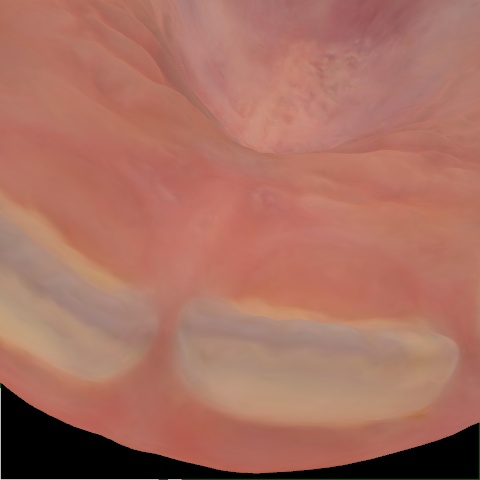

Annotated as "Bad"